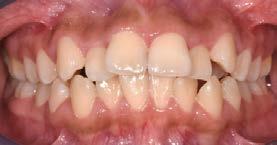

Estudio comparativo, observacional y experimental in vivo. Se empleó en una paciente femenina de 56 años de edad; valorada en la clínica de rehabilitación oral del Centro de Estudios Multidisciplinario de Rehabilitación Oral, (CEMRO), en Tarímbaro, Michoacán; quién decidió hacer un cambio en su sonrisa debido a que esta le generaba insatisfacción, cambiando sus restauraciones antiguas, deficientes en el sector anterior; para lo cual se planeó el retiro de 5 coronas de metal-porcelana de los OD 11,12, 13, 21 y 22 vitales, las cuales serán confeccionadas mediante técnica CAD/CAM realizando su historia clínica y autorizando su consentimiento informado.

Se planteó la utilización de cerámica feldespática e-max de la casa comercial Ivoclar Vivadent, en la presentación de bloques para la realización de las coronas totales en los OD

11, 12 y 13 mediante técnica CAD/ CAM, en su versión HT, color A2. Por otro lado, las otras 2 coronas de los OD 21 y 22 fueron confeccionadas con disco de zirconia Zahndent en tono A2. Estas fueron puestas a prueba mediante la aplicación Adobe Photoshop, con ayuda de una fotografía de las coronas tomada antes de su cementación definitiva, y una segunda medición con las coronas ya cementadas, únicamente se realizó el análisis en los OD 11 Y 21, los cuales fueron cementados con cemento translucido Multilink Speed de Ivoclar Vivadent, se tomaron fotografías con cámara profesional Cannon T8 y lente macro 100mm. Es importante mencionar que decidí utilizar cemento dual translucido para evitar alteración en el color de las coronas ya cementadas, con el fin de obtener mediciones puntuales de color y determinar las cantidades de pigmento que hay en cada corona mediante un fondo negro y así poder corroborar que se logró un buen mimetismo. El tiempo estimado para el procedimiento fue de 5 citas.

Se realizó un segundo análisis con las coronas ya cementadas en boca, únicamente de los incisivos centrales superiores, ya que uno fue confeccionado con disilicato de litio y el otro con zirconio. En este caso obtuvimos como resultado en la corona de disilicato de litio: del color rojo: 172, del color verde: 148 y en cuanto al color azul: 123. En la corona de zirconio obtuvimos del color rojo: 171, del color verde: 143, y del color azul: 119; en la escala de 0 a 255 que arroja la aplicación de Adobe Photoshop.

Podemos afirmar que también hubo variación y a pesar de utilizar 2 tipos de cerámicas diferentes, se logró obtener un buen mimetismo, dando como resultado un resultado satisfactorio para la paciente.

Figura 3. Coronas ya cementadas.